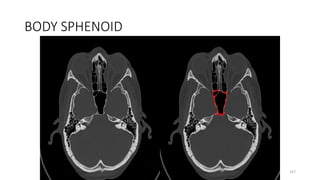

SPHENOID BONE BODY

BODY SPHENOID

SPHENOID BODY